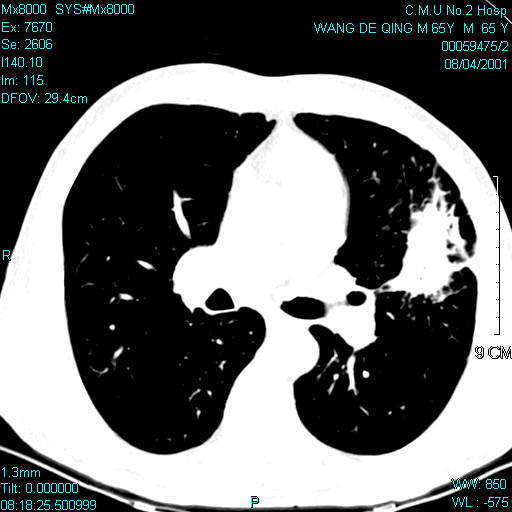

男,65

左肺舌叶可见不规则形高密度影,密度不均,其内可见小泡征,边缘呈浅叶,有毛刺及胸膜凹陷征.考虑周围型肺癌.

首选考虑左上肺舌段慢性炎性肿块,依据:周边肺野欠清,病灶与胸膜牵扯太多,周边见多发细支气管扩张,局部可见纤维条块及瘢痕旁气肿,左肺门不大。但还是要与肺癌区别。

左肺舌叶不规则肿块影,内可见小泡影,边缘见浅分叶,可见血管集束征,胸膜牵拉征,考虑周围性肺癌

很支持lkc8963的高见!周边见多发细支气管扩张基本可以排除周围型肺癌(原来有过沉痛的教训,对这个印象比较深刻,呵呵。)。

当然,不能完全排除周围型肺癌。如果是肺癌的话,那么腺癌的可能性略大一些。

病灶形态不规则,周围见纤维条索,胸膜牵拉,左侧胸廓略塌陷,考虑是慢性过程,支持慢性炎症。

病灶内见多发小空洞,首先考虑结核,建议查痰

考虑机化性肺炎,周边不规则,呈长毛刺状,与肺癌的毛刺征还是有区别的。

首先考虑炎性肿块,依据:病灶大体呈梭形,虽有长短不一的毛刺,但边缘大部较清晰,且毛刺多较长,不是那种细密毛刺,并有索条影与肺门及邻近胸膜粘连,肺门和纵隔内未见明显肿大淋巴结。

但考虑到病人年龄、发病率及没有明显慢性炎症史,不完全排除周围型肺癌。